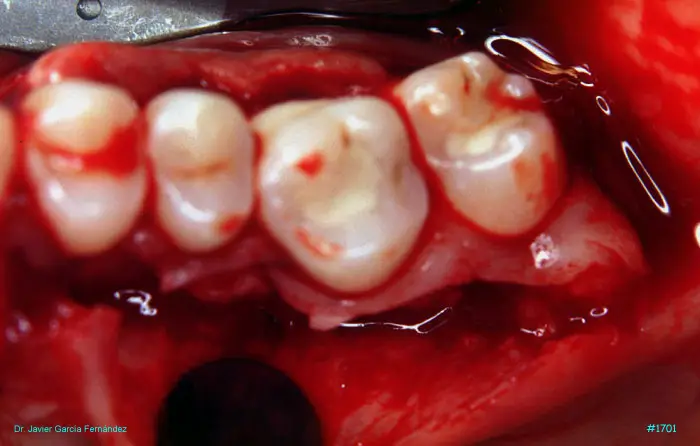

Atlas of Surgical Techniques in Periodontics. Chapter IV. Atlas de Técnicas Quirúrgica en Periodoncia

image 212